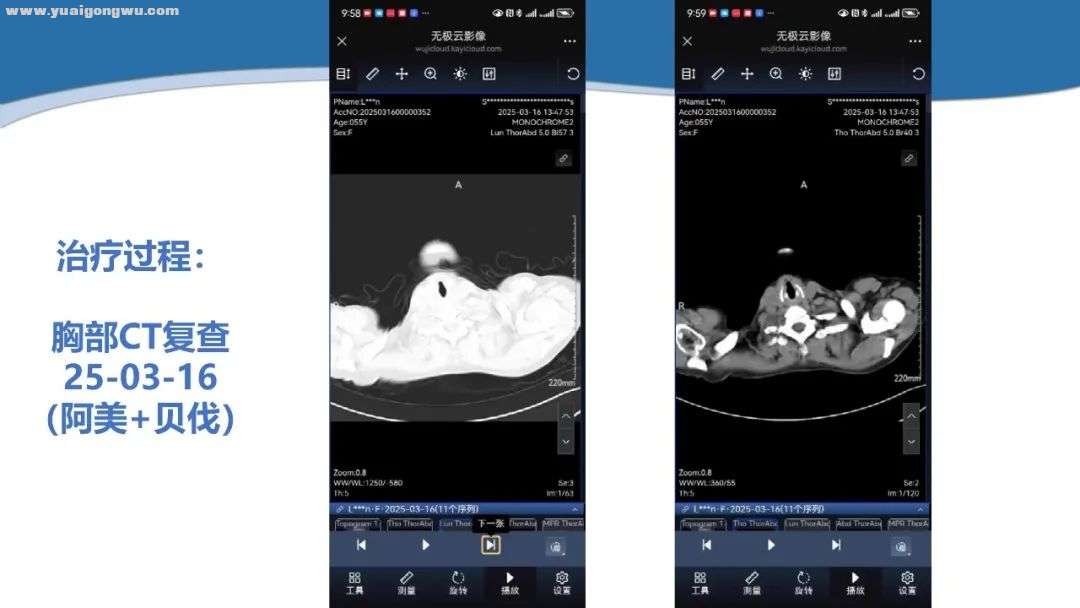

侯代伦教授 胸部CT两次检查结果变化不大,2024年11月至2025年3月胸腔积液量略有增加。虽肺内病灶是通过电脑传输影像查看,并非完全数字化影像,但更值得关注的是脑部磁共振变化。目前影像显示,患者左侧基底节区病灶较前增大,2025年3月15日与 2024年8月20日相比,病灶增大,增强扫描有血供且略增强,FLAIR成像呈高信号,范围也增大,由此判定颅内病变进展。